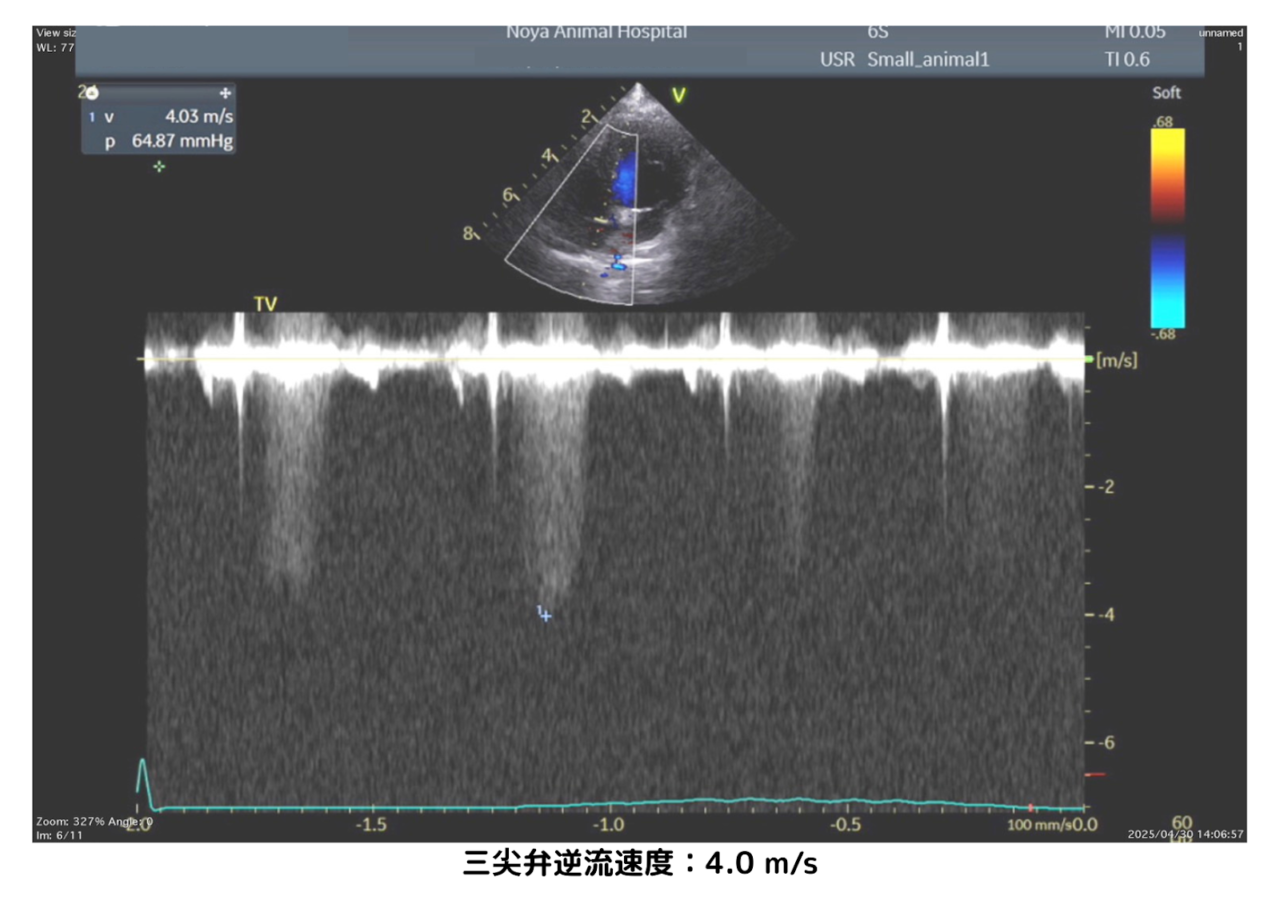

さらに「三尖弁(さんせんべん)」という右心室と右心房の間にある弁を通る血液の逆流(逆流速度)を測定し、肺動脈の圧力を推定します。

肺高血圧症では、肺の血管に強い圧力がかかることで右心室から血液を送り出す力(=右心室圧)が高くなります。右心室圧は肺動脈圧とほぼ同じため、三尖弁からの逆流速度を測ることで肺動脈の圧力を間接的に知ることができるのです。

実際には肺動脈の圧を直接測るにはカテーテル検査が必要ですが、動物医療では体への負担が大きいため、心エコーで得られる三尖弁逆流の速度(例:4.0m/sなど)から肺動脈圧を間接的に評価するのが一般的です。